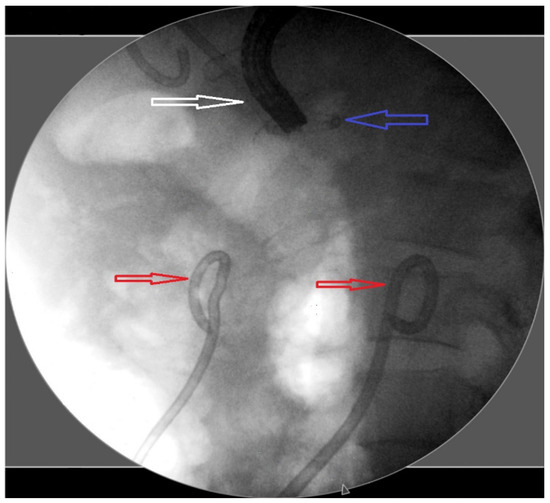

2. Materials and Methods

3.3. The Addition of Percutaneous Intervention as a Step-Up Approach

3.4. Outcomes of Complications, Recurrence, and Follow-Up